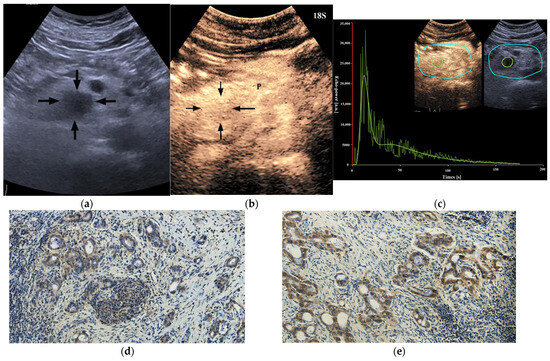

Figure 5. A 60-year-old male patient with a pancreatic ductal adenocarcinoma. (a) US revealed a hypoechoic lesion (arrows) at the pancreatic head. (b) The lesion (arrows) showed iso-enhancement of PED on CEUS. P = normal pancreatic parenchyma. (c) Time intensity curve analysis demonstrated a higher peak enhancement value (21,946.5 [a.u.]). (d) Photomicrographs of immunohistochemistry stain sections demonstrated a HIF-1α high expression ductal adenocarcinoma (original magnification, ×200). (e) Photomicrographs of immunohistochemistry stain sections demonstrated a GLUT1 high expression ductal adenocarcinoma (original magnification, ×200).

3.6. Correlations between CEUS Quantitative Perfusion Features and the Expression of HIF-1α and GLUT1 of PDAC

A quantitative analysis of CEUS was performed using the Software VueBox Quantification Toolbox (version 4.3). A total of 72 of 102 lesions obtained the ROIs parameters. Among the 72 cases of PDAC, 24 cases showed both high HIF-1α and GLUT1 high expression, 21 cases showed both low HIF-1α and GLUT1 low expression, 12 cases showed high HIF-1α but GLUT1 low expression, and 15 cases showed low HIF-1α but GLUT1 high expression. Both HIF-1α-high PDACs and GLUT1-high PDACs showed higher peak enhancement (PE) (p = 0.024 and p = 0.018, respectively) (Figure 5 and Figure 6) and higher wash-in rate (WIR) values (p = 0.015 and 0.002, respectively) (Table 5) more frequently. There were no significant differences in rise time (RT), time to peak (TTP) and wash-in area under the curve (WiAUC) between HIF-1α or GLUT1 high and low expression PDACs (p > 0.05 for all).